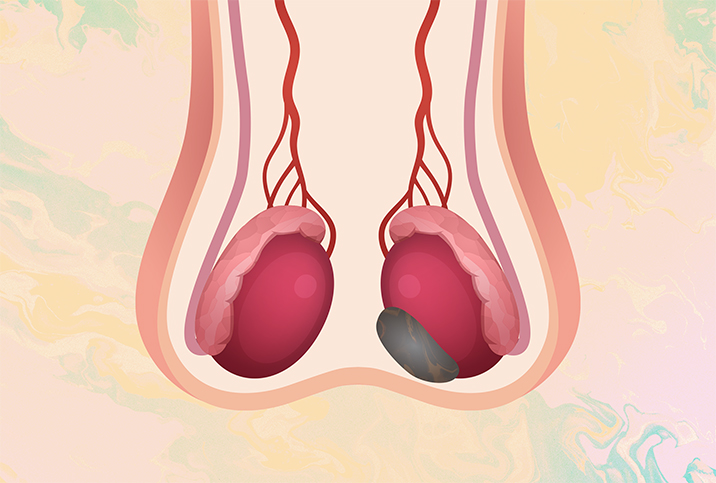

Conditions with similar symptoms

Testicular cancer shares some symptoms with epididymitis, an infection of the epididymis, the storage tube for sperm situated at the back of each testicle. Epididymitis often causes pain and enlargement of the testicles or swelling in the scrotum from inflammation. The testicles may feel hot to the touch, and potential urinary problems include pain during urination or discharge.

Fortunately, imaging can set the diagnosis straight. In an ultrasound, epididymitis generally looks different from a testicular tumor, Haywood said. Epididymitis also improves through treatment with antibiotics; if it doesn't improve, your doctor may have concern about an underlying tumor.

Haywood added that some testicular tumors are benign, or noncancerous, and do not spread to other parts of the body. But if your doctor sees a tumor on an imaging test, they often surgically remove the testicle even though the tumor is sometimes benign—biopsies are not typically done on testicular tumors because they risk spreading the cancer.

In another case of is-it-or-isn't-it-cancer, some men with chronic pelvic pain syndrome (CPPS) will experience dull pain in the testes. Again, an ultrasound helps differentiate this condition from testicular cancer because there won't be a mass on the testicle with CPPS.